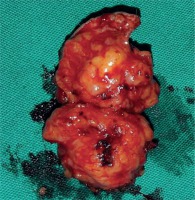

Paragangliomas have rich vascularization and they are hemorrhagic tumors; for this reason a hemovac drain (10 Fr) was placed in the pleural cavity. Active drainage was not detected in the days following surgery. The hemovac drain was removed on the postoperative second day and the patient was discharged on the same day. Pathology was reported as paraganglioma with a central necrotic area of 8 mm in diameter at the size of 4.1 × 2 × 1.8 cm (Fig. 2). Anti-SDHB markers were positive in the immunohistochemical examination. We could not get an image of the pathology because the technical resources in our hospital were insufficient. Antihypertensive treatment was discontinued when the patient had no hypertension on his first month of follow-up. At the 24-hour urine delivered during the second month of follow-up, the VMA value reached normal levels (5.1 mg/24 hours). The patient was followed up by thorax CT taken every 6 months for 2 years. At the end of the first and second year, VMA values were checked against the risk of malignancy and recurrence (1st year value: 4.9 mg/24 hours, 2nd year value: 3.4 mg/24 hours).